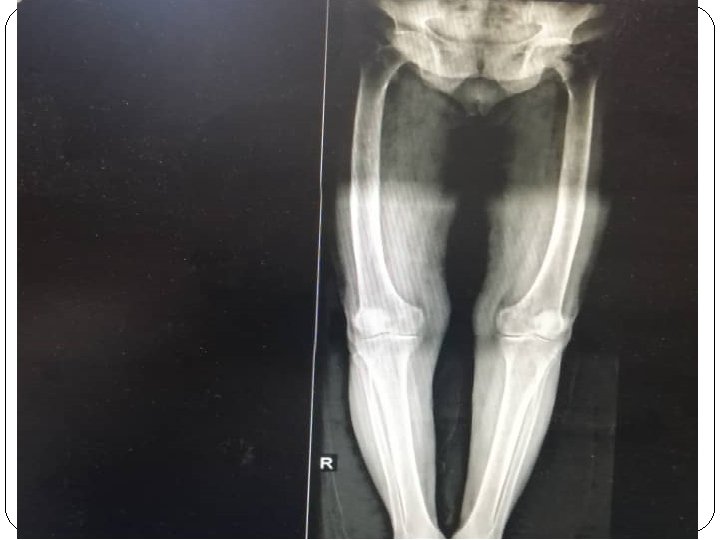

She had intermittent flank pain and hematuria from 2 years ago. She had also epigastric pain from 6 months ago exacerbating with eating and not improved with PPI. She had constipation from many years ago and hadn’t diarrhea, history of fx, weight loss, polyuria and polydipsia Because of right lower thigh pain and her laboratory(ca: 10. 3, p: 2. 9, PTH: 440, 25(OH)Vit. D: 15)wi th primary hyperparathyroidism diagnosis admitted to Taleghani hospital for further workup and treatment.

Imaging report